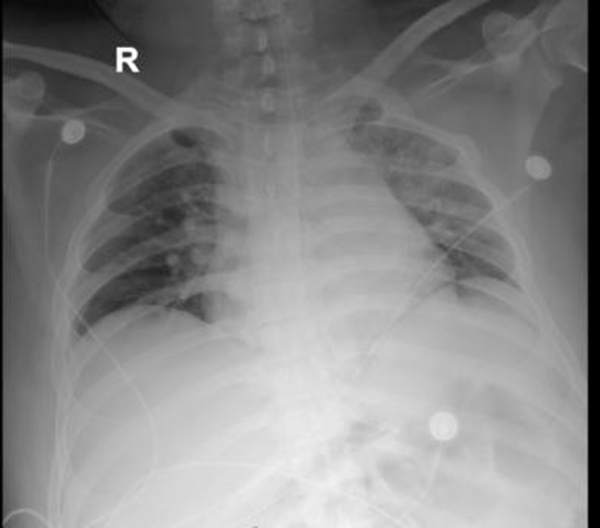

后續(xù)給與積極抗感染等治療,復(fù)查胸片示左肺不張改善,體溫正常,炎癥指標(biāo)下降,再次復(fù)查氣管鏡下可見痰量較前明顯減少,總體病情好轉(zhuǎn),4月23日轉(zhuǎn)到普通病房繼續(xù)治療;颊呒覍俦硎荆氜D(zhuǎn)三家醫(yī)院就醫(yī),還是徐醫(yī)附院最值得信任,對(duì)呼吸ICU全體醫(yī)護(hù)人員表達(dá)了敬意和衷心感謝。